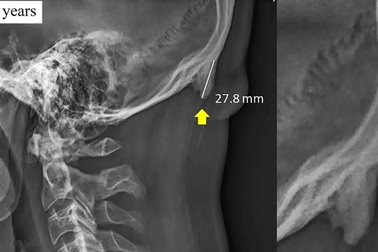

“Mọc sừng” do dán mắt vào điện thoại có nguy hiểm không?Ngay lúc này có thể bạn đang cúi đầu xem điện thoại và lo lắng về một báo cáo gần đây cho biết nhiều người trẻ đang bị “mọc sừng” trên xương sọ do dành quá nhiều thời gian xem điện thoại.